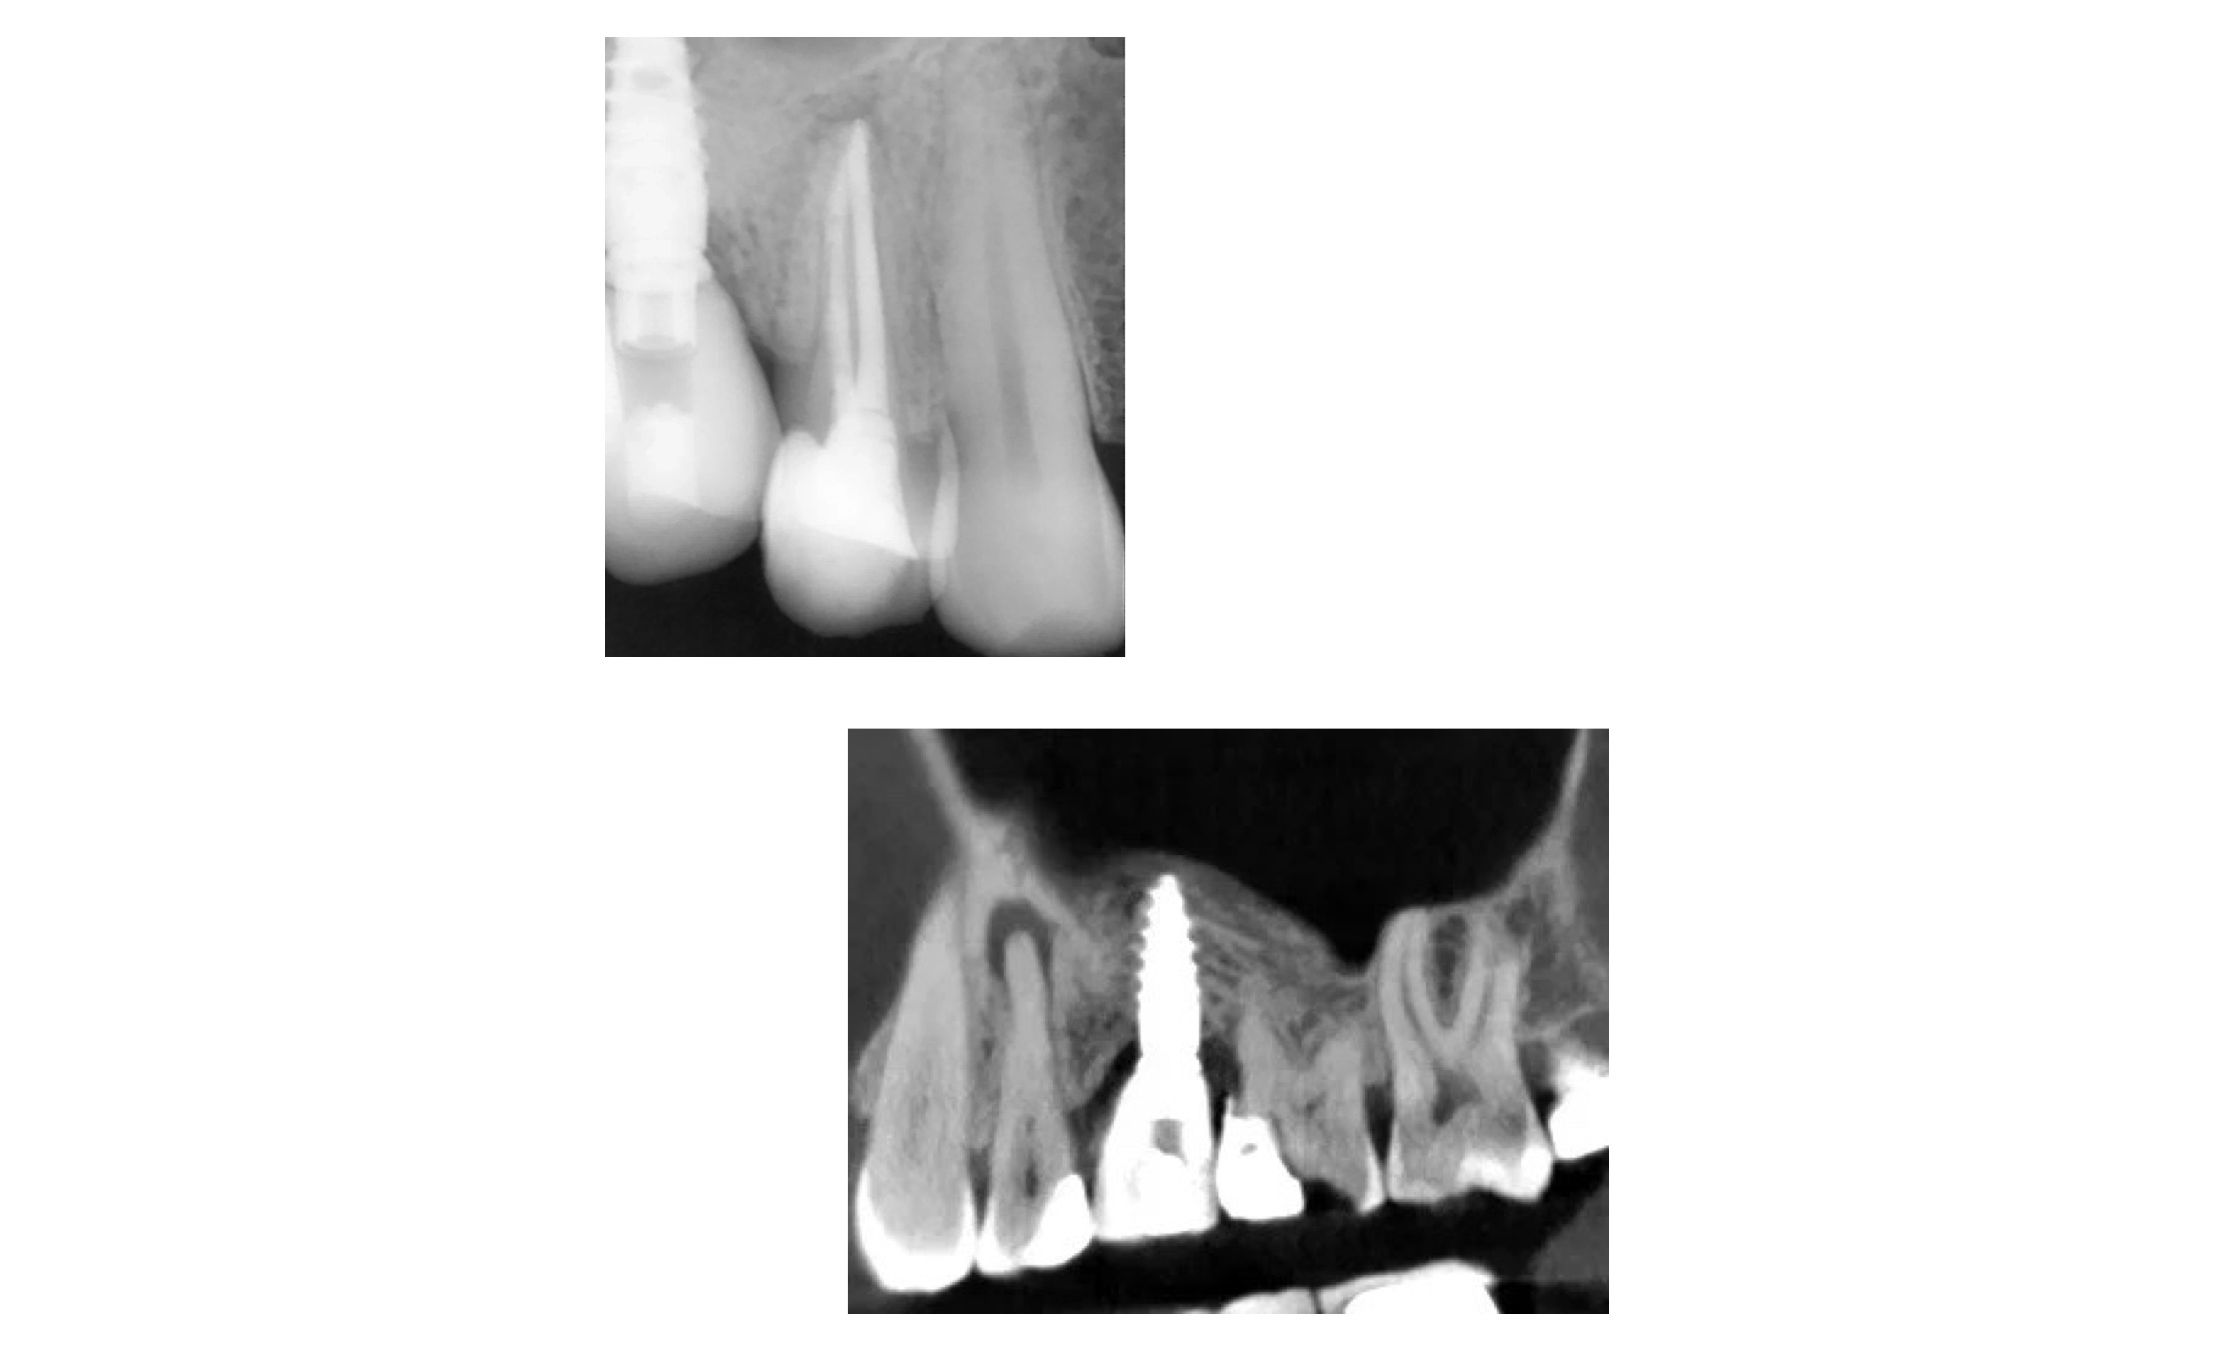

Лечение хронического апикального периодонтита 14 зуба

В карусели кейс врача-стоматолога терапевта-пародонтолога Рахмановой Марины Александровны.